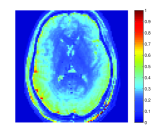

Due to the lack of gold standard maps for this data, we are unable to provide quantitative error results (e.g. NMSE). Therefore, in this experiment we compare between the various algorithms by examining reconstruction results using 400 TRs (representing 40% of scanning time), to quantitative values of brain tissues from the literature. Since the results obtained in the original MRF experiment (using 1000 TRs) mostly correspond to quantitative values from the literature, the maps generated using 1000 TRs using the original MRF algorithm are provided in Fig. 10, for reference.

T1 reference

T2 reference PD reference df reference

The results of T1, T2 and PD maps for BLIP, MBIR-MRF and FLOR appear in Fig. 11. Since IR-bSSFP sequence has been used in this experiment, off-resonance frequency has also been computed and shown. We used 109 different values in the range between -250 and 240 Hz. It can be seen that for T1, all iterative algorithms provide similar results, and T1 values of grey matter (GM), white matter (WM) and cerebrospinal fluid (CSF) regions correspond to similar values that appear in the literature (see Table 1 in Ma et al.Ma et al. [2013]) and in Fig. 10. While T2 results exhibit visible differences between the various methods, WM and GM values for all methods correspond to values that appear in the literature. However, both BLIP and MBIR MRF exhibit T2 values for CSF that are lower than those reported in the literature. This can be seen in Fig. 12, where the color scale for T2 is adjusted to 500-2000ms (T2 values for CSF are around 2000ms). Shortened T2 values in CSF were also reported in the original MRF experiment with 1000 TRs (and were justified as out-of-plane flow in this 2D experiment). In our case, using the same acquired data, it can be seen in Fig. 12 that FLOR provides CSF values that better correspond to literature values, when compared to the other methods.